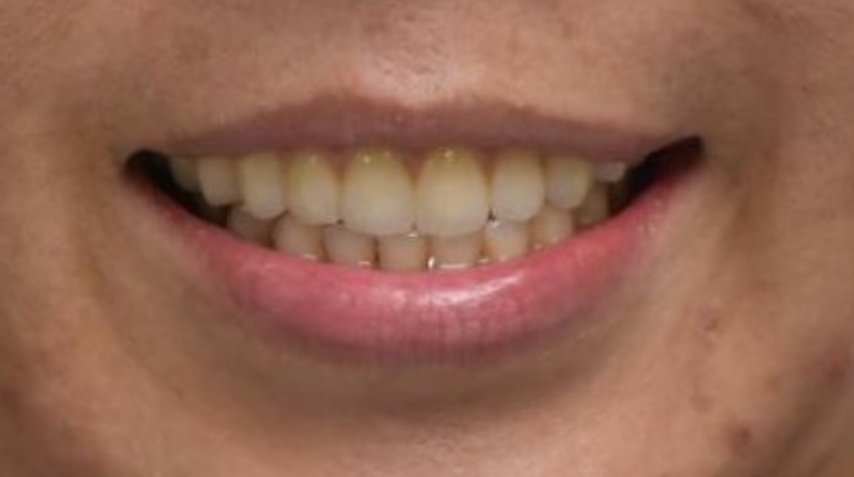

圖:患者許小姐牙齒重建後狀態;術後成功恢復正常咀嚼功能,生活品質大幅提升。